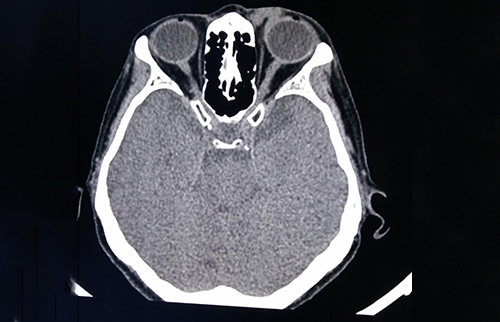

醫(yī)學(xué)影像科